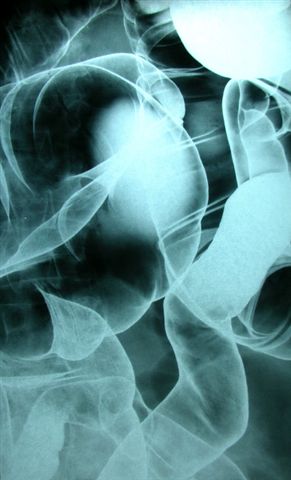

air contrast barium enema devlab MEDEBAR 85 is a 65% w/w barium sulfate suspension with the following indications:

• air contrast radiology of the colon